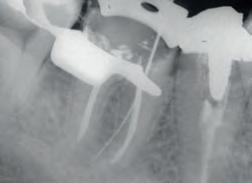

ENDODONTICS • 117–132

Mineral Trioxide Aggregate Repair

Cement

Canal Sealer

Resin-Coated Gutta Percha

File Lubricants

Calcium Hydroxide Paste

Citric Acid

Endodontic Tips Posts and Drills

Light-cured temporary resin